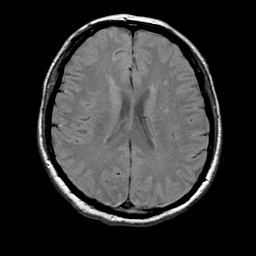

MR Study #1 -- Slice #14

[Home][Help][Clinical][Tour 1] Slice 14